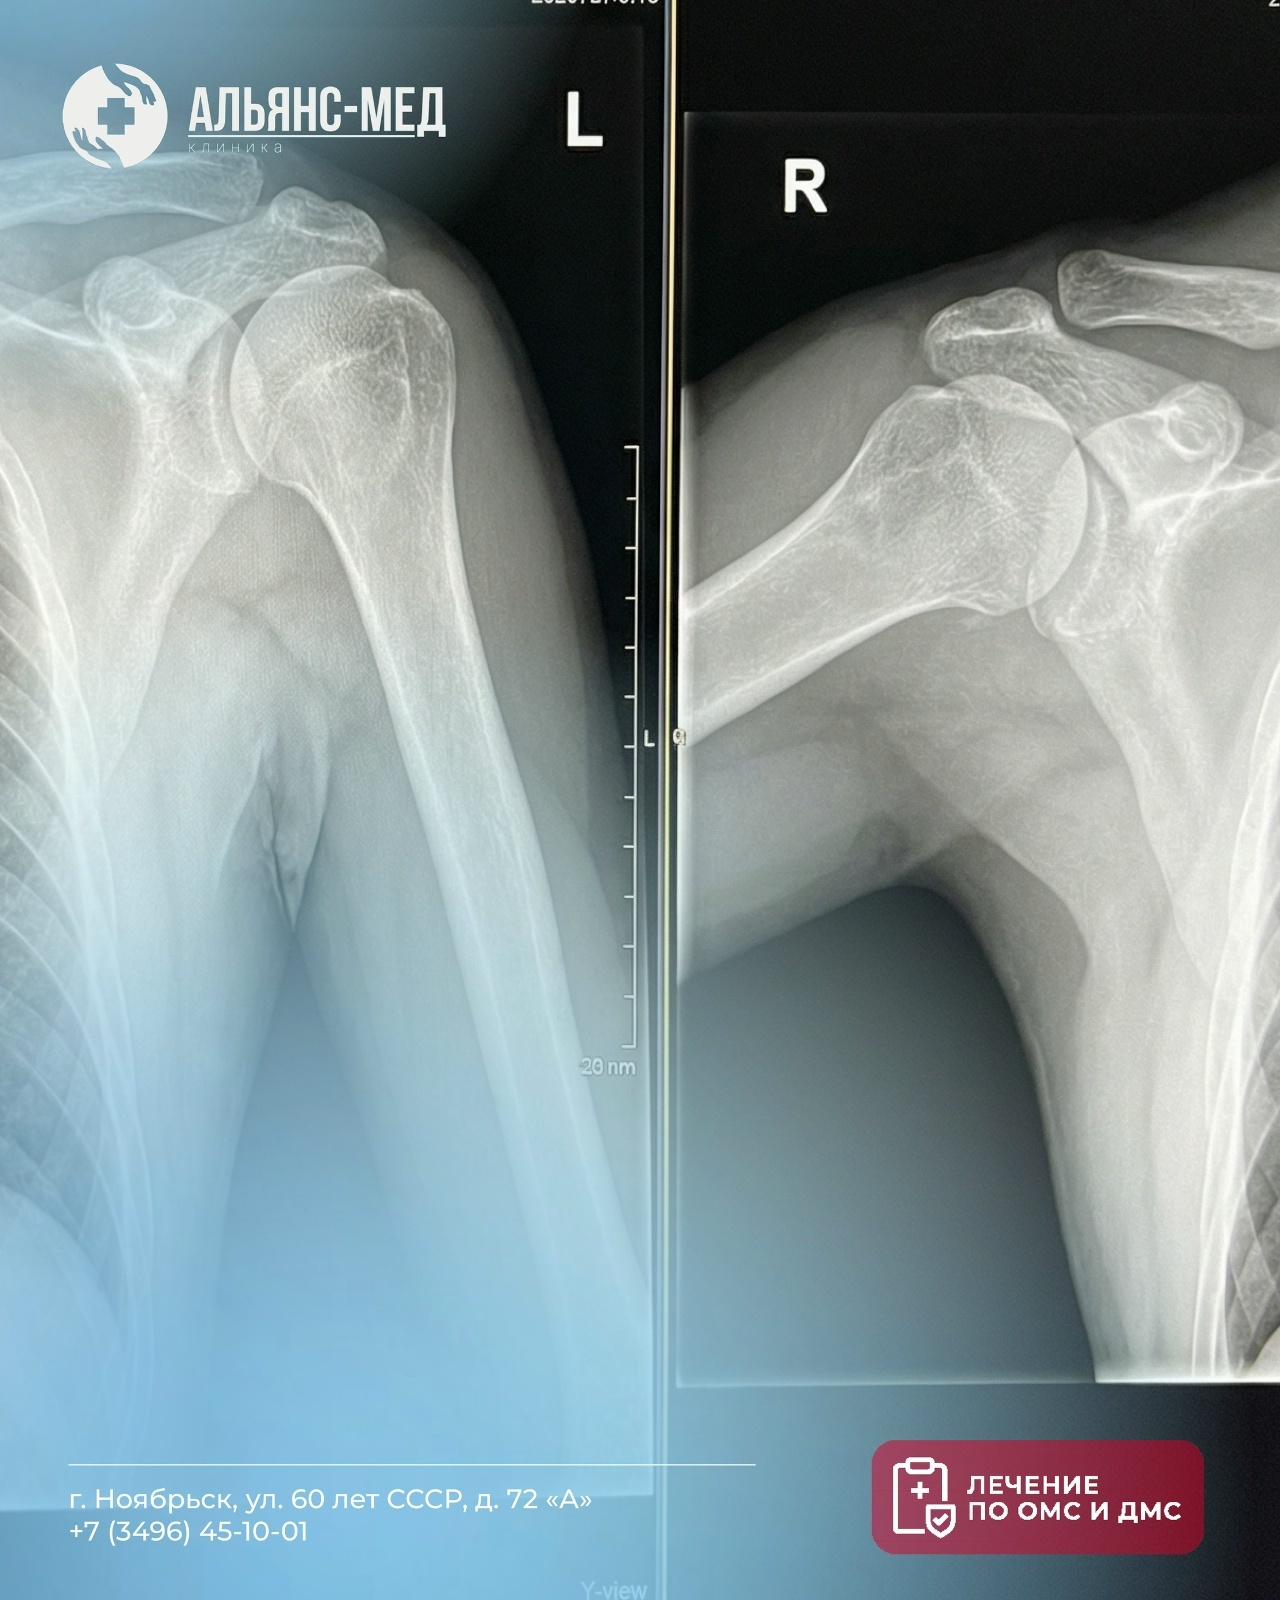

Боль в плече, скованность движений или последствия травмы не стоит игнорировать. Рентген — быстрый и информативный способ понять, что происходит внутри, и вовремя начать лечение

• Выявление переломов, вывихов и посттравматических изменений

• Обнаружение воспалений, артрита, опухолей

• Врач делает снимок в 1–2 проекциях — это занимает всего 10–15 минут

• Уже через четверть часа вы получаете заключение рентгенолога с чёткими рекомендациями